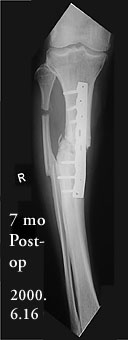

Attached are X-rays of my right leg three months after surgery with Ilizarov fixation.

According to the orthopaedic surgeon, they show solid callus formation on the medial side, while some gaps remain on the lateral side. There is no infection at the wire sites or anywhere else. The frame is to remain attached for one or two months longer. I find it to be much less of a burden than I expected. I am walking with full weight-bearing (no crutches or cane), though not yet with full balance, due to muscle atrophy. My walking is nearly pain-free, except for severe but transient pain in the center of the knee when descending stairs. I believe this is related to the unavoidably high placement of the uppermost wires, and it should cease after the frame is removed. As measured on the X-ray films, the difference in leg length is now five mm, compared with pre-op 3.5 cm. If the tibia continues to solidify and stays in its present configuration after removal of the frame, I will have escaped the judgment of Ecclesiastes 1:15 ('A crooked thing cannot be made straight'). I will inform the List of progress at six months post-op.